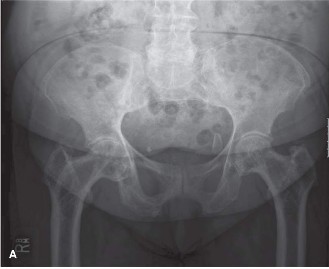

A 72-year-old female presents with progressive bilateral hip and pelvic soreness as well as back pain and hea…